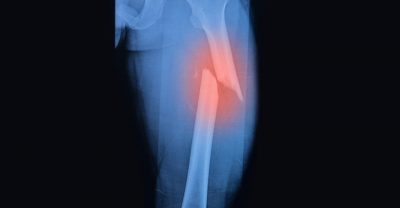

عندما تتعرّض العظام لضغط أكبر من قدرتها على التحمل تصاب بشرخ أو بكسر. وهناك عوامل صحية تؤدي إلى ضعف العظام ونقص كثافتها أو ما يُسمّى “الهشاشة” ما يزيد احتمال الإصابة بالكسور، إليك ما تحتاج معرفته عنها:

* التقدم في السن من عوامل زيادة الهشاشة والترقق، ما يجعل الإنسان عرضة لكسر مع كل سقوط أو إصابة.